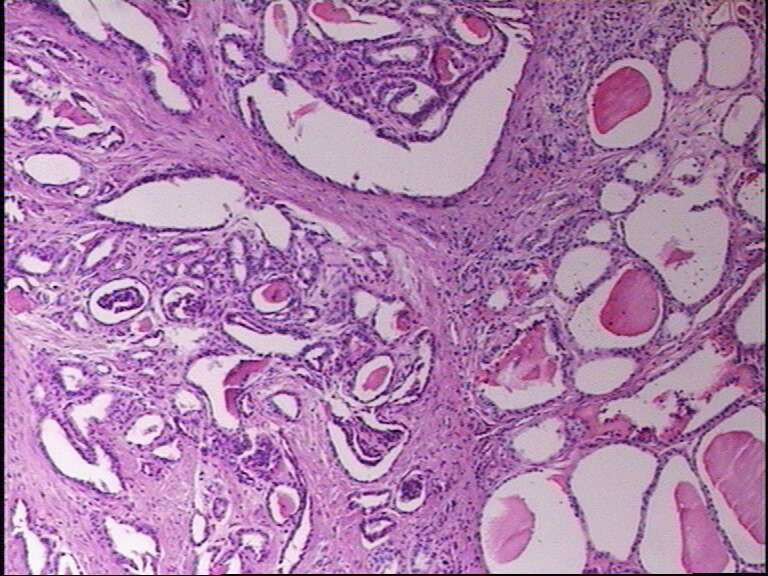

女43岁,甲状腺肿物

就目前的切片看本例没有形成明确的以纤维结缔组织为轴心的乳头结构,前15张图更是连乳头状癌特有的核的表现(核拥挤、核沟、核内假包含体、毛玻璃核等)也不明显,而后传的7张图中核的改变都比前15张图中要明显,个人绝得诊断乳头状癌缺乏重要依据(1)明确的乳头结构(2)核拥挤、核沟、核内假包含体、毛玻璃核,所以希望重取材,多切片搜索可靠的诊断依据再下结论。

呵呵,大家看看够不够乳头状癌?图12-15再清晰些会更好。

乳头状癌:

通过所给图片具备了乳头状结构,也有了核的一些特征,虽不典型:1、核椭圆形,2、核拥挤重叠,3、核上下分层,4、核沟等,可以诊断乳头状癌。

嗯。图不好,不敢妄谈。但乳头相对比较宽大,细胞核大多圆形,可以排除经典型(common type)。